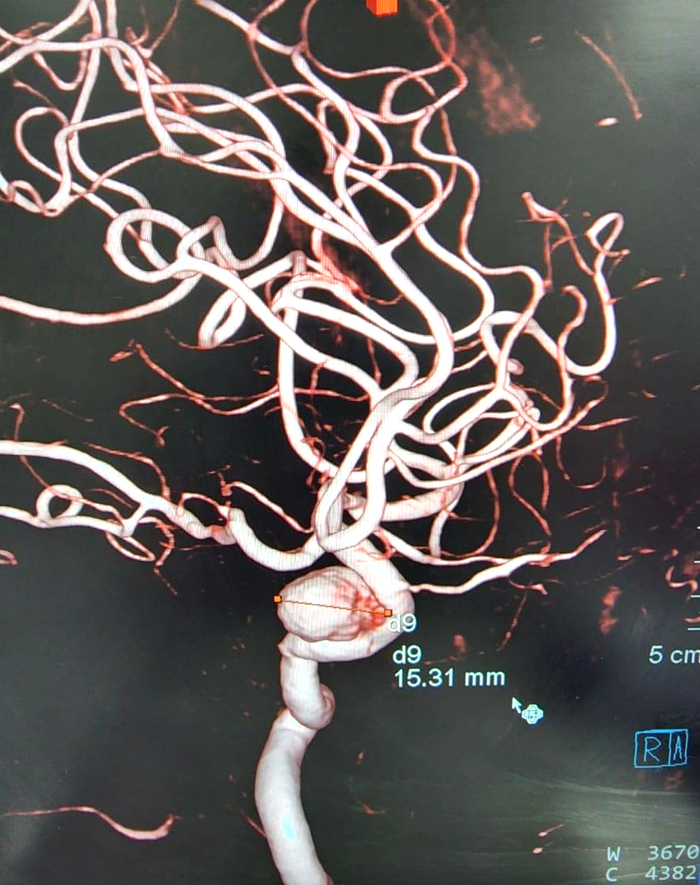

Hình ảnh túi phình mạch não chụp DSA.

Bệnh nhân K. được chỉ định chụp CT dựng hình mạch máu não (CTA) kết quả: Hình ảnh túi phình kích thước lớn động mạch cảnh (ĐMC) trong đoạn xoang hang trái. Bệnh nhân được chỉ định chụp mạch máu não số hóa xóa nền, với kết quả: Túi phình ĐMC đoạn xoang hang kích thước 4.6 x 3.4 mm, bờ nham nhở có nhú;Túi phình ĐMC cảnh đoạn xoang hang kích thước 15 x 13 x 4.6mm, bờ tròn đều. Sau khi hội chẩn với chuyên gia can thiệp nội mạch thần kinh của BV Đại học Y dược (ĐHYD) TP. Hồ Chí Minh, cân nhắc các yếu tố về kích thước, vị trí, hình thái học của túi phình. Ê-kip đã quyết định điều trị túi phình lớn bên trái bằng phương pháp can thiệp nội mạch gồm: stent chuyển dòng và coilling một phần túi phình nhằm ngăn ngừa túi phình vỡ. Chiều ngày 5/5/2022, các phẫu thuật viên (PTV) khoa Ngoại Thần kinh - BVĐK tỉnh Khánh Hòa phối hợp cùng PTV chuyên gia BV ĐHYD TP.HCM, tiến hành can thiệp nội mạch đặt stent chuyển dòng và coilling một phần túi phình. Sau 120 phút ca phẫu thuật kết thúc, bệnh nhân tỉnh táo, glassgow 15 điểm, dấu hiệu sinh tồn ổn định, không yếu liệt tứ chi và được theo dõi tại viện 3 ngày.